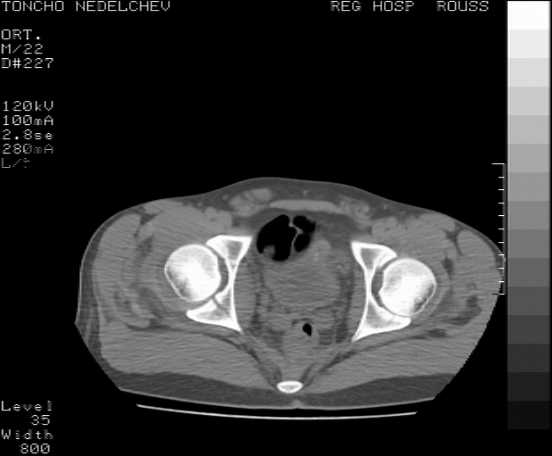

Here are some more axial images. What is your opinion as for the timing of the operative treatment?

posterior approach, ORIF

Yordan! In this case position of bone fragments is quite good. We

prefer to use miniinvasive technique. We fix posterior column by can. screw and put 3mm pin with distal thread to the anterior column. Next day after the surgery he may start walking with crutches. 3 month after the surgery we remove the pin. In cases of maleolar fractures we use

angle stable plates to lat. mal. and pins or screws and if syndesmosis is intact - full loading is not forbidden.